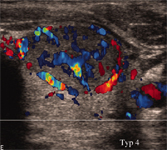

Die Sonographie mit hoch auflösenden Schallköpfen (7,5 bis 12,5 MHz mit Duplex) stellt heute bereits wenige Millimeter große Herdbefune präzise dar. Es existieren sonographische Kriterien, auf deren Basis, maligne Schilddrüsenknoten mit sehr hoher Sicherheit identifiziert werden können. Hierzu gehören unter anderem die Hypoechogenität, die unregelmäßige Randbegrenzung, Mikroverkalkungen sowie eine zentral verstärkte Vaskularisation.